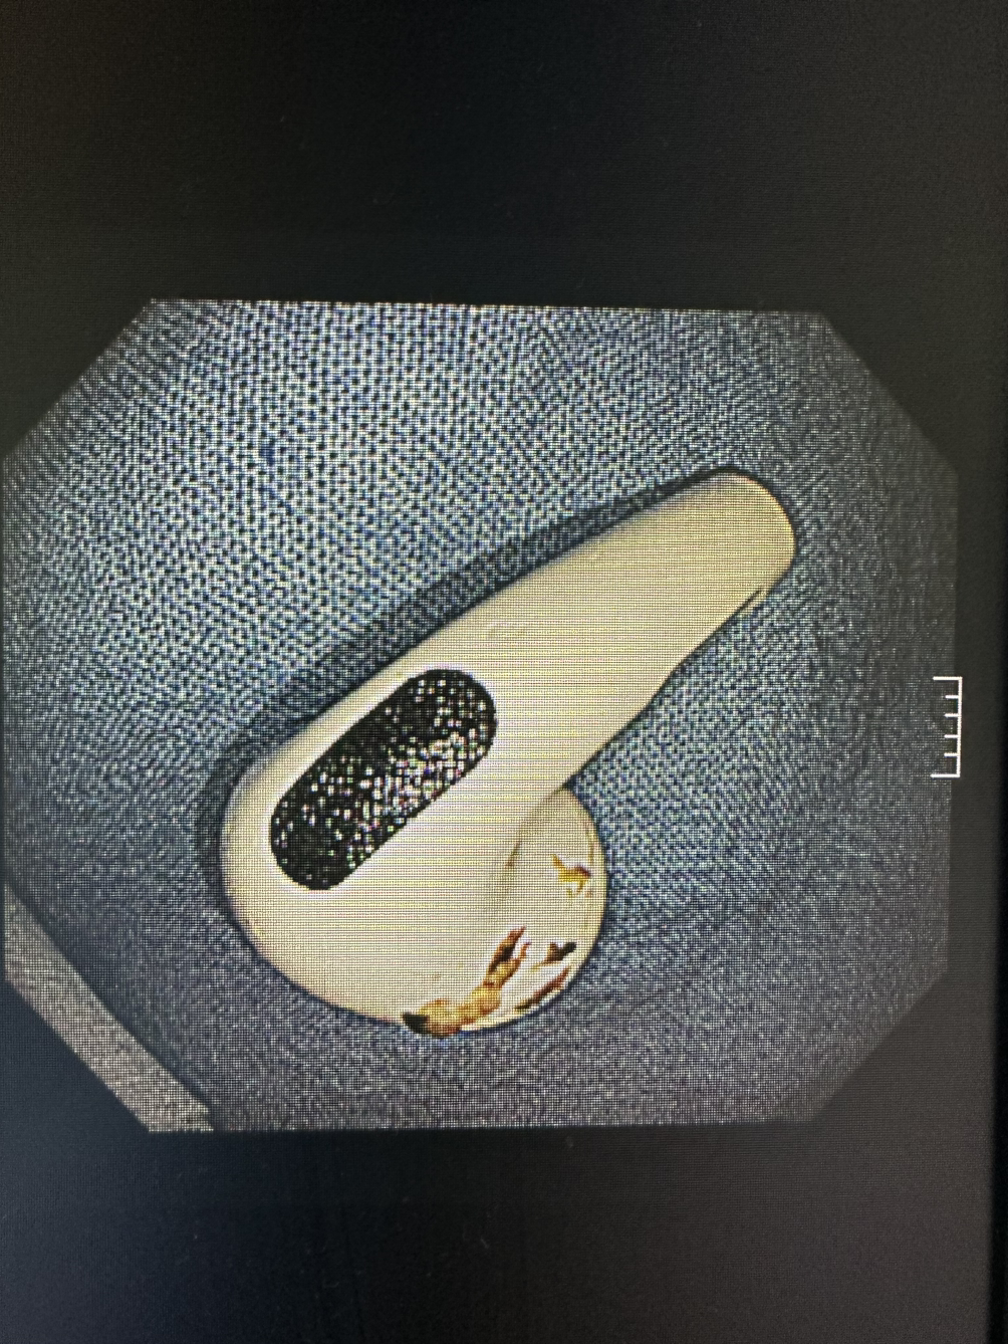

술을 먹고 실수로 삼키고, 약을 껍질채 삼키기도 한다. 이어폰을 삼키고 사탕 막대와 집게도 삼킨다. 기도가 아닌 식도로 들어가서 망정이지 틀니나 치아는 조심해야 한다. 이렇게나 대한민국 국민들은 다채롭게 삼키는구나.

재소자들은 불가능에 도전한다. 칫솔도, 연필도, 뚜껑부터 해서 여러 가지를 삼키고 온다. 여러 가지 추론을 해볼 수 있겠지만 정확한 이유는 그들만이 알 거다. 그들은 여러 명의 교도관을 대동하고 죄수복(?)을 입고 온다. 자주 삼키는 사람도 있었고 수면으로 안 하면 이대로 죽겠다고 소리치는 사람도 있었다. 생의 의지는 생각보다 강하고 그들의 외침은 생존을 향한 몸부림이다. 이러한 이물을 제거하는 이는 정해져 있다. 주로 K교수님이 많이 하고 함께하는 간호사는 나다. 이유는 모른다.